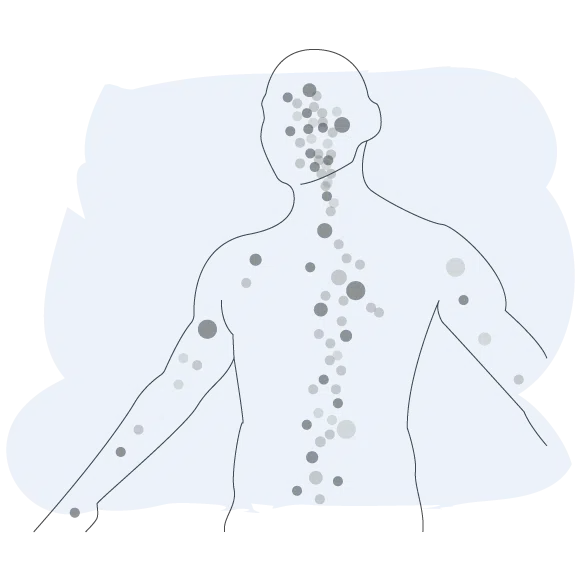

Endokanabinoidų sistema užtikrina organizmo fiziologinę pusiausvyrą.Endokanabinoidų sistema (ECS)

Endokanabinoidai natūraliai susidaro žmogaus organizme

Endokanabinoidų sistema (ECS) aptinkama visuose žinduoliuose. Ji yra būtina vidinei organizmo komunikacijai. Būtent dėl ECS mes nesame tik ląstelių visuma, o tiksliai funkcionuojantis žmogaus organizmas.

Ši unikali sistema dalyvauja daugelyje svarbių organizmo procesų – ląstelių dalijimesi, taip pat smegenų, nervų ir imuninės sistemos veikloje. Ji atlieka svarbų vaidmenį bendroje sveikatoje ir organizmo gebėjime susidoroti su įvairiais su sveikata susijusiais sutrikimais.

ECS sudaro kanabinoidų receptoriai, endokanabinoidai ir fermentai. Svarbiausi iki šiol ištirti endokanabinoidai, kuriuos organizmas gamina pats, yra anandamidas (ANA) ir 2-arachidonoilglicerolis (2-AG) – jie padeda reguliuoti ir palaikyti pusiausvyrą daugelyje organizmo procesų.

Centrinė nervų sistema

Centrinė nervų sistema

Dalyvauja tam tikruose atminties procesuose, taip pat skatina naujų neuronų formavimąsi ir jų apsaugą.

Imuninė sistema

Imuninė sistema

Reguliuoja imuninės sistemos veiklą, slopindama uždegiminių citokinų susidarymą.

Kaulai

Kaulai

Dalyvauja kaulų masės reguliavime ir kaulų atsinaujinimo procesuose.

Virškinimo traktas

Virškinimo traktas

Padeda apsaugoti virškinimo traktą nuo uždegimo ir pernelyg didelės skrandžio ar žarnyno sekrecijos.

Endokanabinoidų sistema

Metabolizmas

Metabolizmas

Palaiko pusiausvyrą, reguliuodamas maistinių medžiagų transportą, energijos kaupimą, maisto suvartojimą ir moduliuodamas jautrumą insulinui.

Raumenys

Raumenys

Padeda didinti ištvermę, reguliuodami cukraus kiekį kraujyje, ir prisideda prie vadinamosios „bėgiko euforijos“.

Odos ligos

Odos ligos

Hormonai

Hormonai

Dalyvauja hipotalamo funkcijose, kurios reguliuoja organizmo reakcijas į stresą, medžiagų apykaitą ir reprodukciją.

Endokanabinoidų sistema (ECS) užtikrina organizmo pusiausvyrą

Veikia panašiai kaip kanabinoidai, esantys CBD produktuose ir kanapių augale.ECS palaiko organizmo pusiausvyrą (homeostazę), dalyvaudama daugelyje gyvybiškai svarbių procesų — ji reguliuoja energijos tiekimą, smegenų veiklą, ląstelių dalijimąsi ir imuninės sistemos aktyvumą, užtikrindama organizmo struktūrinį ir funkcinį stabilumą.

Jei endokanabinoidų sistema neveikia tinkamai, sutrinka ryšys ir signalų perdavimas tarp organų, o tai gali sukelti įvairius funkcinius sutrikimus ir ligas, pavyzdžiui: